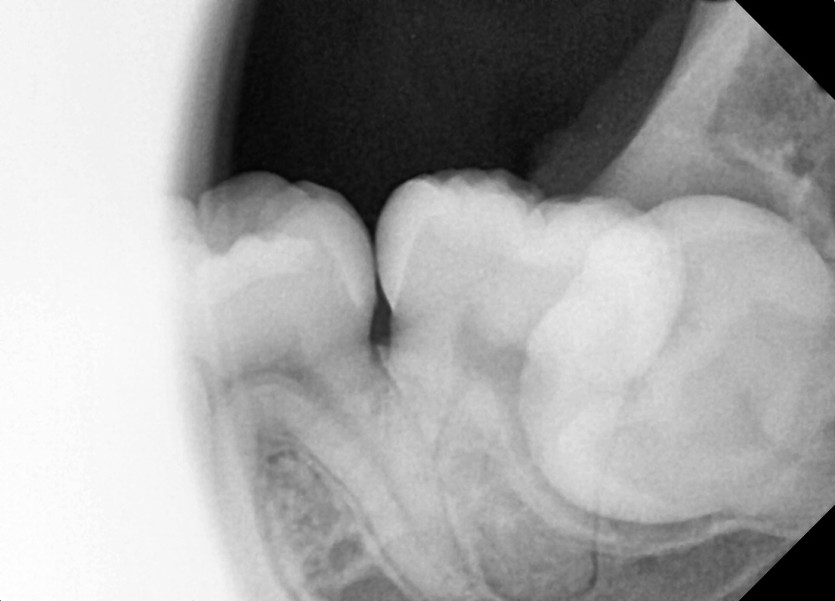

#28,38 사랑니 발치

구강외과 전문의가 당일 발치했습니다.